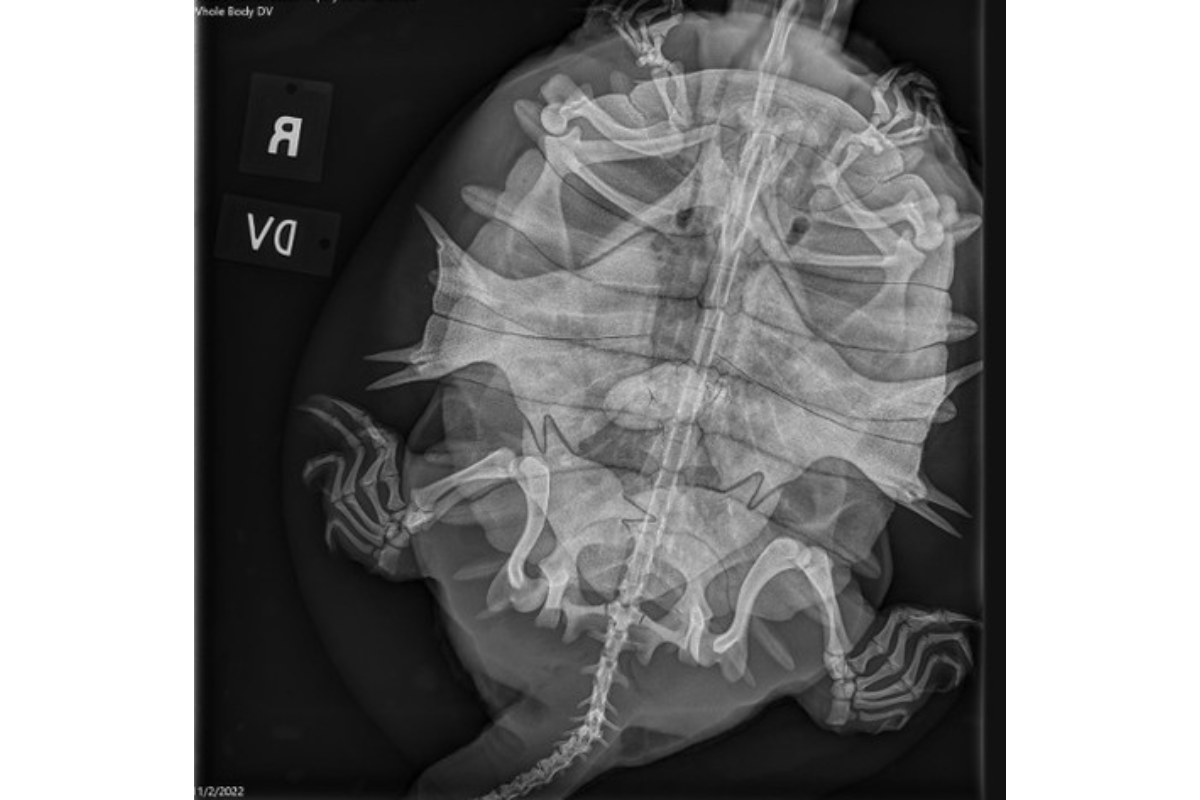

Eastern Spin Softshell Turtle

In similar ponds and lakes, you may find this eastern spiny softshell turtle. The animal likes to find muddy spots and may hibernate there for about half the year.